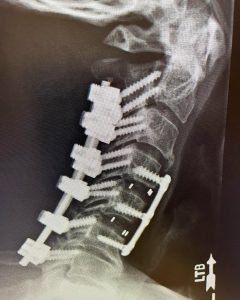

Surgery was be performed to take the pressure off the spinal cord and then realign his spine and stabilize it with both an anterior plate and screws and posterior screws and rods. The final x-ray as a postoperative picture. He did well after surgery and made a complete recovery with a return to normal activities.